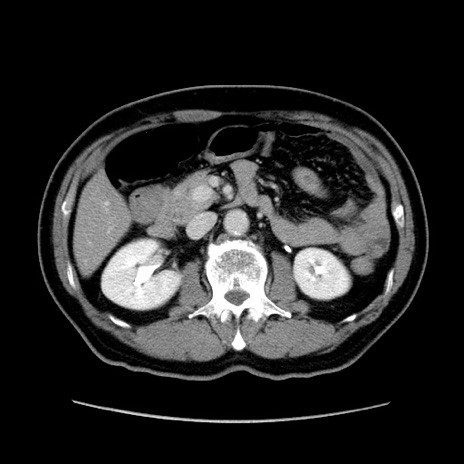

症例34(横断像)

【症例】60歳代 男性

【主訴】右鼠径部膨隆

【現病歴】1年程前より右鼠径部膨隆あり。自己にて還納可能だったため放置していた。3時間前より右鼠径部の脱出を認め、還納困難となり受診。

【既往歴】高血圧

【身体所見】右鼠径部に小児頭大の膨隆あり。弾性硬であり、用手還納は困難。左鼠径部にも膨隆を認める。脱出はなし。

【データ】WBC 15500、CRP 測定なし